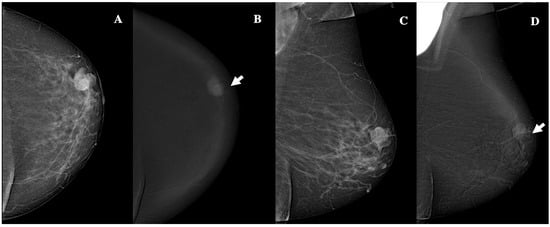

Figure 3.

Contrast-enhanced mammography in a 60-year-old patient with BI-RADS 4 lesion. CEM revealed a 19 mm oval lesion with circumscribed margins, heterogeneous enhancement, and low conspicuity. Panel (A) shows the craniocaudal low-energy image, while Panel (B) displays the corresponding recombined image (white arrow). Panel (C) depicts the mediolateral oblique low-energy image and Panel (D) shows the recombined mediolateral oblique (MLO) image (white arrow). Histopathology identified the lesion as an invasive, grade 1, Luminal-A ductal cancer, without lymphovascular invasion.